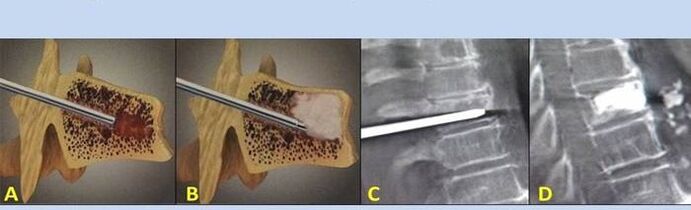

- Nukleoplastik – Entfernung des Bandscheibenkerns. Die Operation entlastet die Nervenenden.

- Punktion Vertebroplastie – Methode zur Stabilisierung der Wirbel. Während des Eingriffs füllt der Arzt die Wirbelsäulenhöhlen mit Knochenzement.